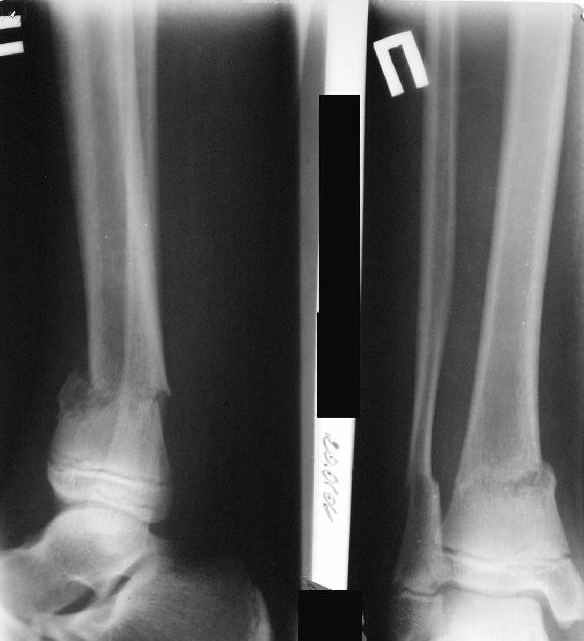

Нашел в комп-ре схожий случай:

1) з/репозиция, 2) фиксация 2 спицами, 3) аппарат, 4) фиксационные

спицы удалены...

См. аттачт.

А можно было наложить аппарат и по поводу ложного сустава...

По крайней мере не было бы укорочения (пусть и в 2 см)...